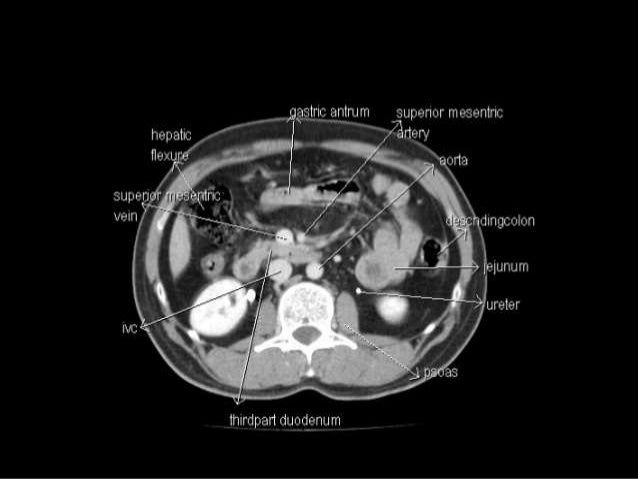

Anatomy of abdomen ct